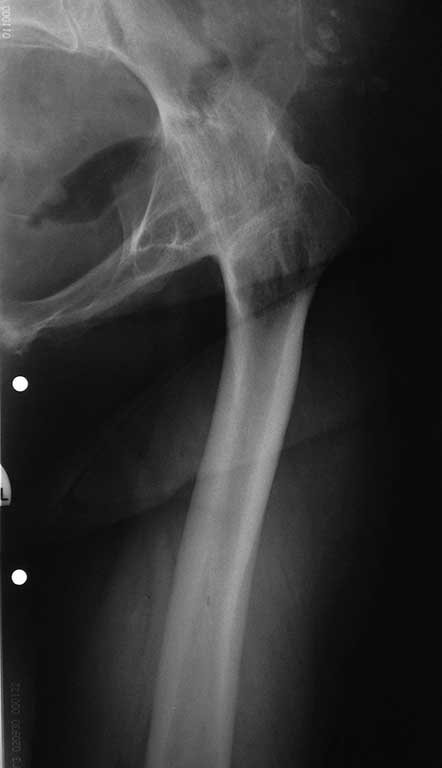

Рентгенологически костный анкилоз. Клинически сгибательно-приводящая контрактура. Ходит без средств опоры с выраженной хромотой. Больна с 10 летнего возраста. Сейчас пациентке 63. Жалуется на умеренные боли в области анкилозированого сустава, хотя складывается впечатление, что болевой синдром обусловлен позвоночником. Если у вас есть опыт операций при подобной деформации посоветуйте оперировать или нет.Выкладываю рентгеновские снимки. Могу выложить данные компьютерной томографии и видео походки.

В прикреплённом файле очень похожее клиническое наблюдение. Пациентке на момент операции 59 лет. Прошло 4 года. На мой вопрос о спине, которая болела перед операцией, она по телефону ответила: А причём тут спина, вы же мне ногу лечили, а спина меня уже не беспокоит. Восстановление функции сустава произошло в течении 6 месяцев. На днях обещала подойти, если так, представлю более демонстративную видеоинформацию. С уважением В.Б.Абдуев